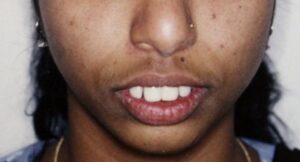

The department caters to patients from different parts of Goa and strives to realise the triple goals of balanced facial proportions, good dental occlusion and optimal oral function through the utility of Orthodontic and Orthopedic devices (wires). The department treats patients with malaligned, spaced and/or protruded teeth.

In addition, the department also helps in the rehabilitation of patients with jaw deformities, including cleft lip and palate. With recent advances in materials and technology, the department is able to cater to all age groups, ranging from 7-65 years and palate patients.

- Combination of braces and jaw surgery for correction of severe deformities, including patients with cleft lip and palate.

- Department of Orthodontics takes an active role in the interdisciplinary management of patients with cleft lip and palate.